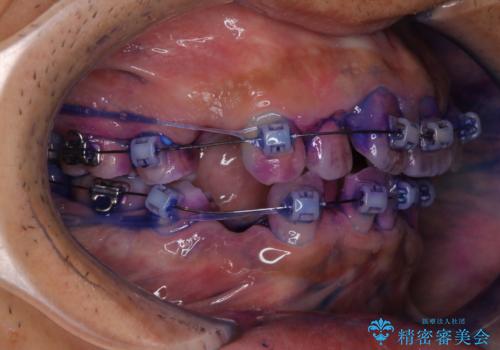

- ワイヤー装置で矯正中の方です。歯磨きがしずらく、専門的な機械でクリーニングしてほしいとの事でした。PMTC60分コースを行いました。

ワイヤー矯正中はブラッシングが難しくなるため、磨き残しが多くなることがあります。適切な道具を使って、適切なブラッシング方法を習得することで、磨き残しを減らすことができます。

また、矯正で歯の移動があると今までなかったところに隙間が出てきたり、ガタつきが解消されてきたりすることで、お口の中の環境が変わります。

矯正治療中も清潔な口腔内を保つことは、とても大切です。そのため、定期的に専門的な機械・材料を使用したProfessinnalcleaning(pmtc)を行うことがおススメです。